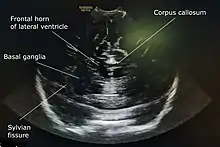

Coronal anterior section through anterior fontanelle of a one-year-old girl.

A 5 to 7.5 MHz probe is used to scan deeper structures in the brain. A 7 to 12 Mhz probe is used for scanning superficial structures for detecting lesions between the brain and the skull, superior sagittal sinus thrombosis, cerebral oedema, and evaluating the structures of sulci and gyri.[4]

A standard cranial ultrasound examination usually involves recording of approximately 11 views of the brain from different angles, six in the coronal plane and five in the sagittal and parasaggital planes.[7] This allows all parts of the ventricles and most of the rest of the brain to be visualised.